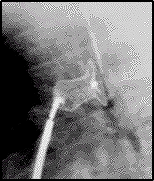

c. Chụp buồng tim: bằng cách bơm trực tiếp thuốc cản quang vào ống động mạch ở t thế ngang 900. Nếu nghi ngờ hẹp eo ĐMC cũng chụp ĐMC ở t thế này. Đóng ống động mạch cũng dùng t thế này nhng bơm thuốc từ ĐMC sang ĐMP.